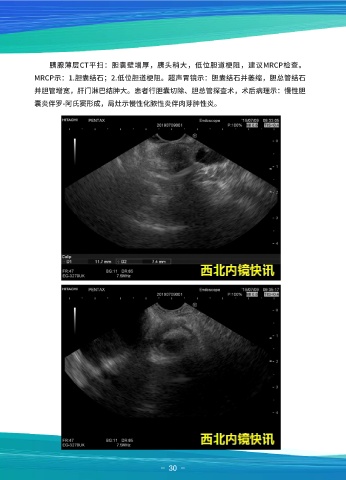

MRCP示:1.胆囊结石;2.低位胆道梗阻。超声胃镜示:胆囊结石并萎缩,胆总管结石

并胆管增宽,肝门淋巴结肿大。患者行胆囊切除、胆总管探查术,术后病理示:慢性胆 患者女,59岁,超声内镜示:见胆总管最宽7mm,胰管最宽5mm,向下追踪见乳

囊炎伴罗-阿氏窦形成,局灶示慢性化脓性炎伴肉芽肿性炎。 头部低回声椭圆形占位,截面直径11mmx7mm,血供丰富。换用十二指肠镜观察,见

乳头呈盘状增生,表面粗糙,胰管开口受压,活检质软。胆囊体积增大。活检提示腺瘤。